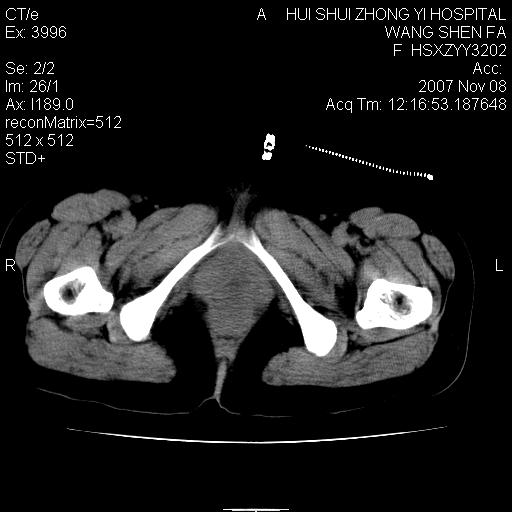

标题: CT10389:女,38岁,腹部巨大包块 [打印本页]

标题: CT10389:女,38岁,腹部巨大包块

腹部巨大包块半年,质硬,边界不清。

多发子宫肌瘤可能性大,建议增强扫描.右侧肾盂\\输尿管积水.

腹腔及盆腔内可见巨大软组织肿物影,内部密度欠均匀,边界尚清晰,周围组织受压移位明显,膀胱前上移位,右侧输尿管受压明显,上端扩张肾盂轻度积水。考虑:1卵巢病变可能性大,囊腺癌>卵巢癌>囊腺瘤.2 子宫病变,子宫肌瘤?